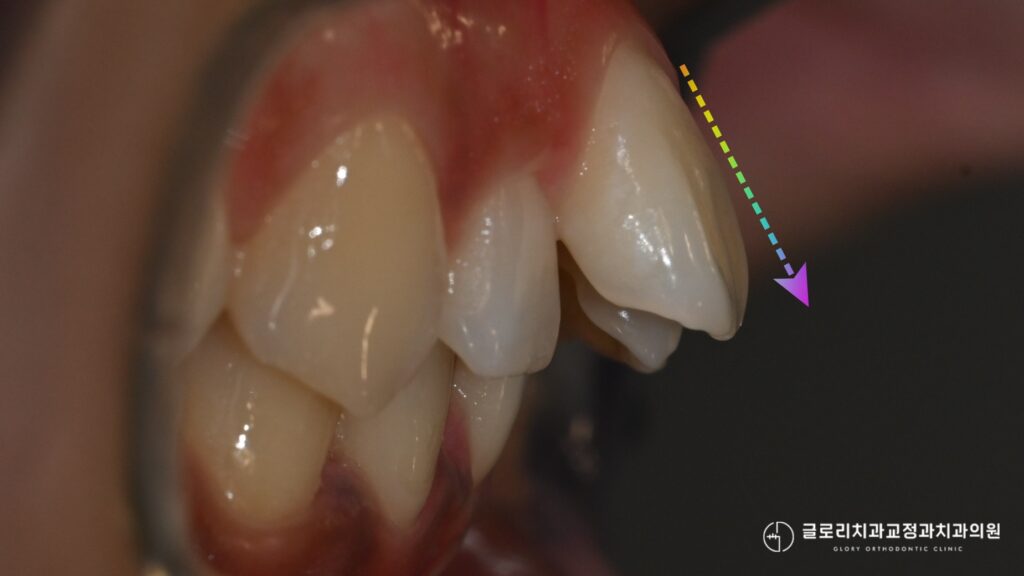

앞니가 앞으로 밀려 나오거나

송곳니가 튀어나오는 현상도

이러한 공간 부족에서 비롯되는

경우가 적지 않습니다.

이때 단순히 치아만 이동시키면

뿌리가 잇몸뼈 바깥으로

벗어날 가능성이 있어

근본적인 접근이 필요합니다.